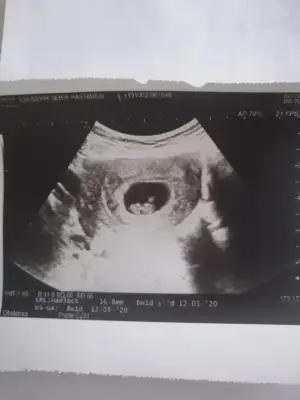

Banada erkek demiştiniz hatta baya net erkek demiştiniz kız diyince doktor şaşırmıştınız bnde çok şaşırmıştım tabi çünkü baya umutlanmıştım 2 kızım var doğal olarak değişik olsun istemiştim tabiki Rabbim in dediği olur ama hala erkek hissediyorum ayrıntılıda pozisyonu tersti cinsiyeti gözükmüyor demişti perinatolog ama 2 doktor kız gibi biride düşük kalitede bir cihazda kız demişti sonra rüyamda bebeğimin isminin koyulduğunu gördüm mavi nüfus kağıdında Ali arif yazıyordu bilemiyorum hala erkek hissediyorum pembe kıyafetleri almama rağmen

az kaldı sonucu görmeye herşey den önce Rabbim sağlıklı ve hayırlı evlatlar nasip etsin bizlere